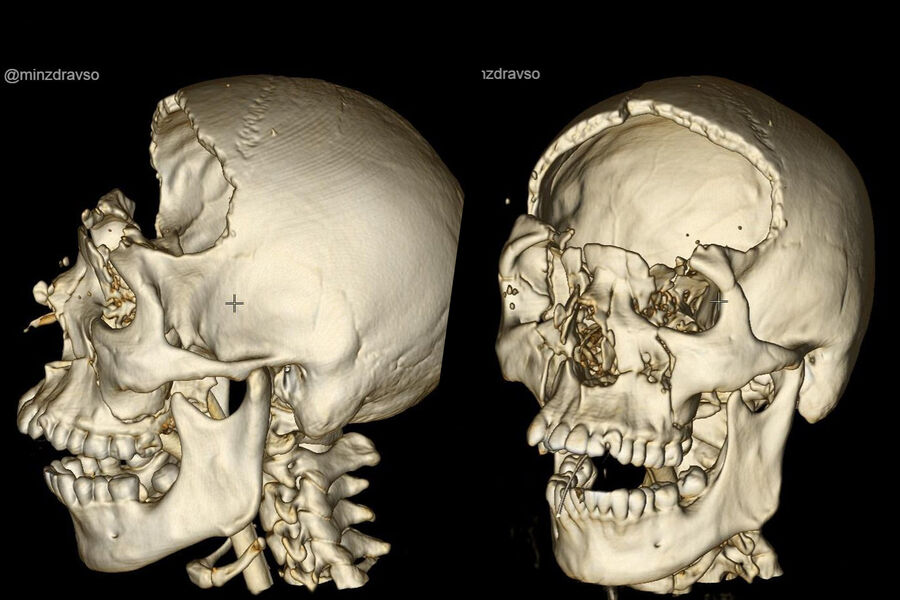

Молодой человек поступил в учреждение после аварии с раздробленным черепом и сразу был направлен на экстренную операцию.

Во время 2,5-часового вмешательства нейрохирурги провели бифронтальную трепанацию, остановили кровотечение, удалили гематому объемом 50 миллилитров, сделали пластику мозговой оболочки. По информации ведомства, благодаря слаженным и своевременным действиям специалистов удалось избежать тяжелых неврологических осложнений.